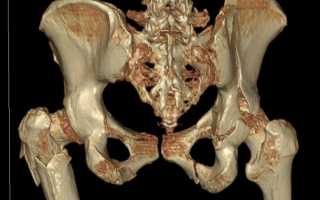

Как делают рентген тазобедренного сустава

Чтобы получить исчерпывающие сведения о состоянии пациента, ему делают обзорную рентгенограмму таза в прямой проекции. Проведение рентгенографии только одного сустава является ошибкой. Для полноценного анализа рентгенологу необходимо видеть снимки обоих ТБС. Часто выявить патологию ему помогает именно сравнение.

- Проведение исследования. Для получение обзорной рентгенограммы пациента укладывают на спину. Таз исследуемого не должен наклоняться и поворачиваться. Чтобы получить правильное отображение шеечно-диафизарного угла, рентгенолог разворачивает обе стопы больного кнутри на 15 градусов. Установив рентгеновскую трубку, он выходит из комнаты и делает снимок.

Рис 1. Укладка пациента при выполнении обзорной рентгенографии в прямой проекции.

- а — положение исследуемого и расстояние до рентгеновской трубки;

- b — направление луча при исследовании.

Помимо обзорного снимка, пациенту также делают рентгенографию больного сустава в боковой проекции. Существует несколько методик его получения. Выбор какой-либо из них зависит от того, какие структуры сустава требуется визуализировать. Исследование может проводиться как стоя, так и в лежачем положении.